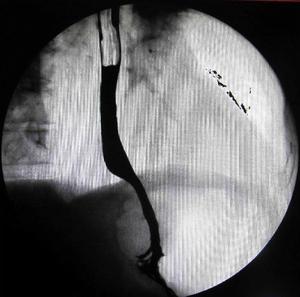

食管裂孔疝X線鋇劑造影:

胃黏膜呈幕狀牽引食管裂孔疝X線鋇劑造影:膈上見胃囊食管裂孔疝 X線鋇餐造影:Schatzki環上移,胃黏膜上牽內腔鏡是診斷食管裂孔疝僅次於放射學檢查的方法。纖維胃鏡較金屬硬管鏡檢查時安全、痛苦小,並可同時檢查胃和十二指腸,以排除引起胃壓升高的因素,且可多次使用,檢查方便。如有裂孔疝時可見食管下括約肌鬆弛,呼氣和吸氣時均呈開放狀態。正常情況下吸氣時食管胃交界點下降,如有疝則不變位,食管鏡內出現胃液的水平較正常時高。如為返流性食管炎時,通過胃鏡可觀察到紅斑、潰瘍的數目、嘗試及其排列情況,潰瘍出血,黏膜糜料及縮穿等。如果經過呼吸周期而賁門呈開放狀,這是返流的另一指征。如病人主訴主要是吞咽困難,套用於“丁”字手法,從下面觀察賁門,也許可以排除早期癌在此區的存在,將胃鏡後退到食管。細心地逐步檢查十分重要。如發現食管縮窄及嚴重食管炎,或懷疑有Barrett柱狀上皮,應作多處活檢,食管潰瘍也可以發生惡性變。當不能排除癌,則使用金屬硬鏡作深部活檢以明確診斷。對某些食管縮窄的病例,在初次作內腔鏡檢查時,可進一步明確診斷及觀察擴張的療效。如懷疑返流,或發現裂孔疝而無返流症狀,放射造影也無返流徵象,應考慮行食管功能檢查。當病人的主訴是吞咽困難時,鋇餐造影和內腔鏡檢查優於食管功能試驗;當吞咽困難不是一個主要症狀,鋇餐檢查雙陰性,則首先考慮作食管功能試驗,明確診斷後也許避免作內腔鏡檢查。食管功能檢查可在門診完成,包括食管測壓、標準酸返流檢查、利用PH電極放在食管內作酸清除試驗和酸灌注試驗。對較複雜的病例,可住院作長時24hpH監測和連續測壓,以提供更多的資料。